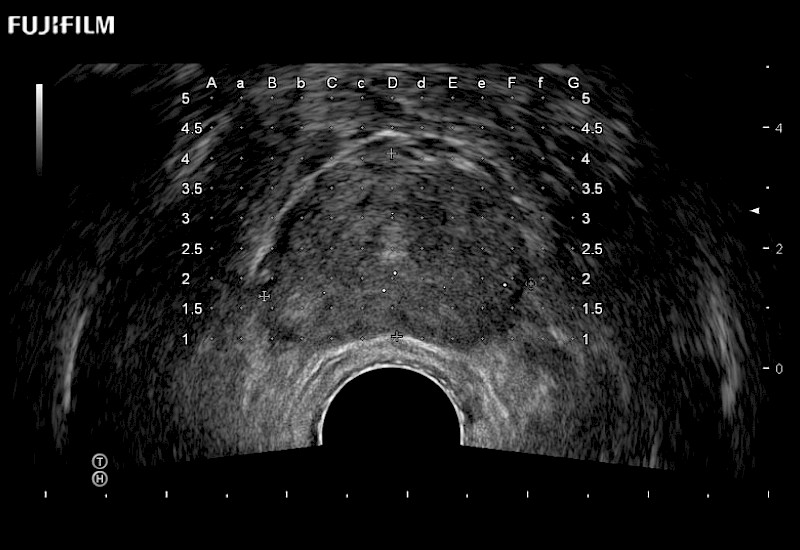

Exclusive 200° FOV end-fire prostate biopsy transducer.

Main Specifications:

Provides real-time imaging of both the sagittal and transverse planes